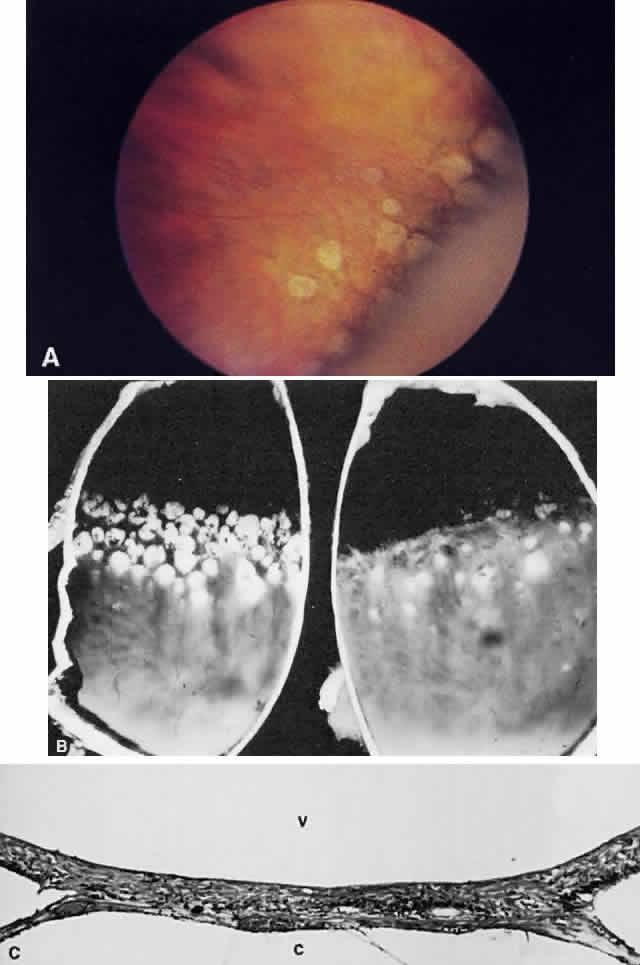

In contrast to lattice degeneration, which affects the inner retinal layers, paving stone degeneration (cobblestone degeneration, peripheral chorioretinal degeneration) affects the outer retinal layers.24 Ophthalmoscopically, paving stone lesions appear as well-demarcated concave zones of depigmentation (Fig. 62A and B). Frequently, the depigmentation is so marked that the larger, outermost choroidal vessels may be seen running through the lesion. The lesions usually are located just posterior to the ora serrata. These depigmented zones may appear individually or may coalesce into larger lesions that demonstrate a scalloped border with pigmented edges.

Fig. 62. A. Paving stones just anterior to the ora serrata. (William Benson: Wills Eye Atlas of Ophthalmology, Fig. 4-58. Philadelphia, Lippincott-Raven, 1996) B. Photograph of the calottes of an autopsy eye showing paving stone degeneration. C. Photomicrograph of paving stone degeneration. The vitreous (v) and choroid (c) are marked for orientation. The retina is detached by an artifact, except in the zone of the paving stone lesion. Notice that the photoreceptors are present to either side of the lesion but not within the lesion. The pigment epithelium also is absent in the area of the lesion. The ophthalmoscopist therefore looks through transparent retina onto choroid and sclera, which accounts for the color of the paving stone lesion.

Histologically, there is loss of the outer retinal layers, including the retinal pigment epithelium (see Fig. 62C). The loss of pigment epithelium accounts for the color of the lesion and permits the larger choroidal vessels to be viewed ophthalmoscopically. The thinned neurosensory retina is firmly adherent to underlying Bruch's membrane and to the reactive pigment epithelium at the margins of the lesion. The pigment epithelial changes account for the clinically observed black border of these zones. Unlike retinal lattice degeneration, there is no change in the overlying vitreous and no pathogenic relation to retinal detachment. In fact, the histopathologic appearance of paving stone degeneration resembles the chorio-retinal adhesion seen after therapeutic cryopexy. The forward advance of a retinal detachment does not extend beyond the posterior edge of a paving stone lesion.